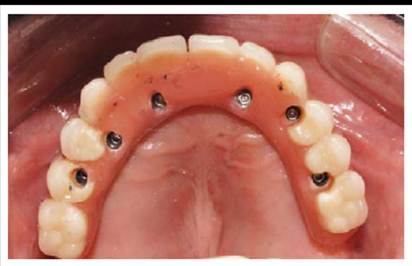

De acuerdo al protocolo reverso y al examen tomo-gráfico (Figura 2) con las guías multifuncionales mantuvimos la planificación inicial de realizar una prótesis híbrida superior implanto soportada sobre 6 implantes y 3 implantes en el maxilar inferior (Figura 3 ),

Figura 3 a y b. Colocación de tornillos de cicatrización.

Debido a que en el maxilar superior se usó hueso liofilizado y al bajo torque del implante a nivel de la pieza 23 se esperó la oseointegración por 6 meses para proceder a la rehabilitación implantosoportada (3era fase). En el maxilar superior se probaron y torquearon los mini pilares CM , con un torque de 15N para mini pilares angulados y 32N para mini pilares rectos.

Figura 7 a Instalación de la prótesis híbrida superior